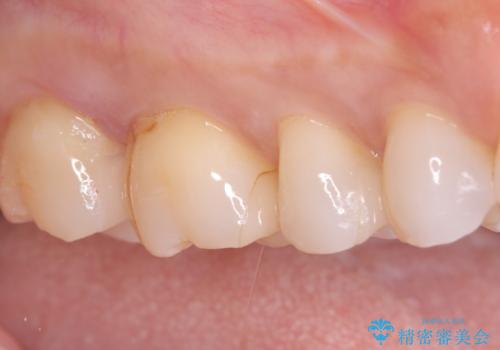

- 昔入れたメタルインレーの下にむし歯が再発したため治療を行った患者様です。

フロスなどの日常の清掃はもちろん不可欠ですが、メタルインレーより汚れが付着しずらいセラミックインレーにて今回は治療を行いました。

セラミックインレー装着時はラバーダムを使用して行っています。